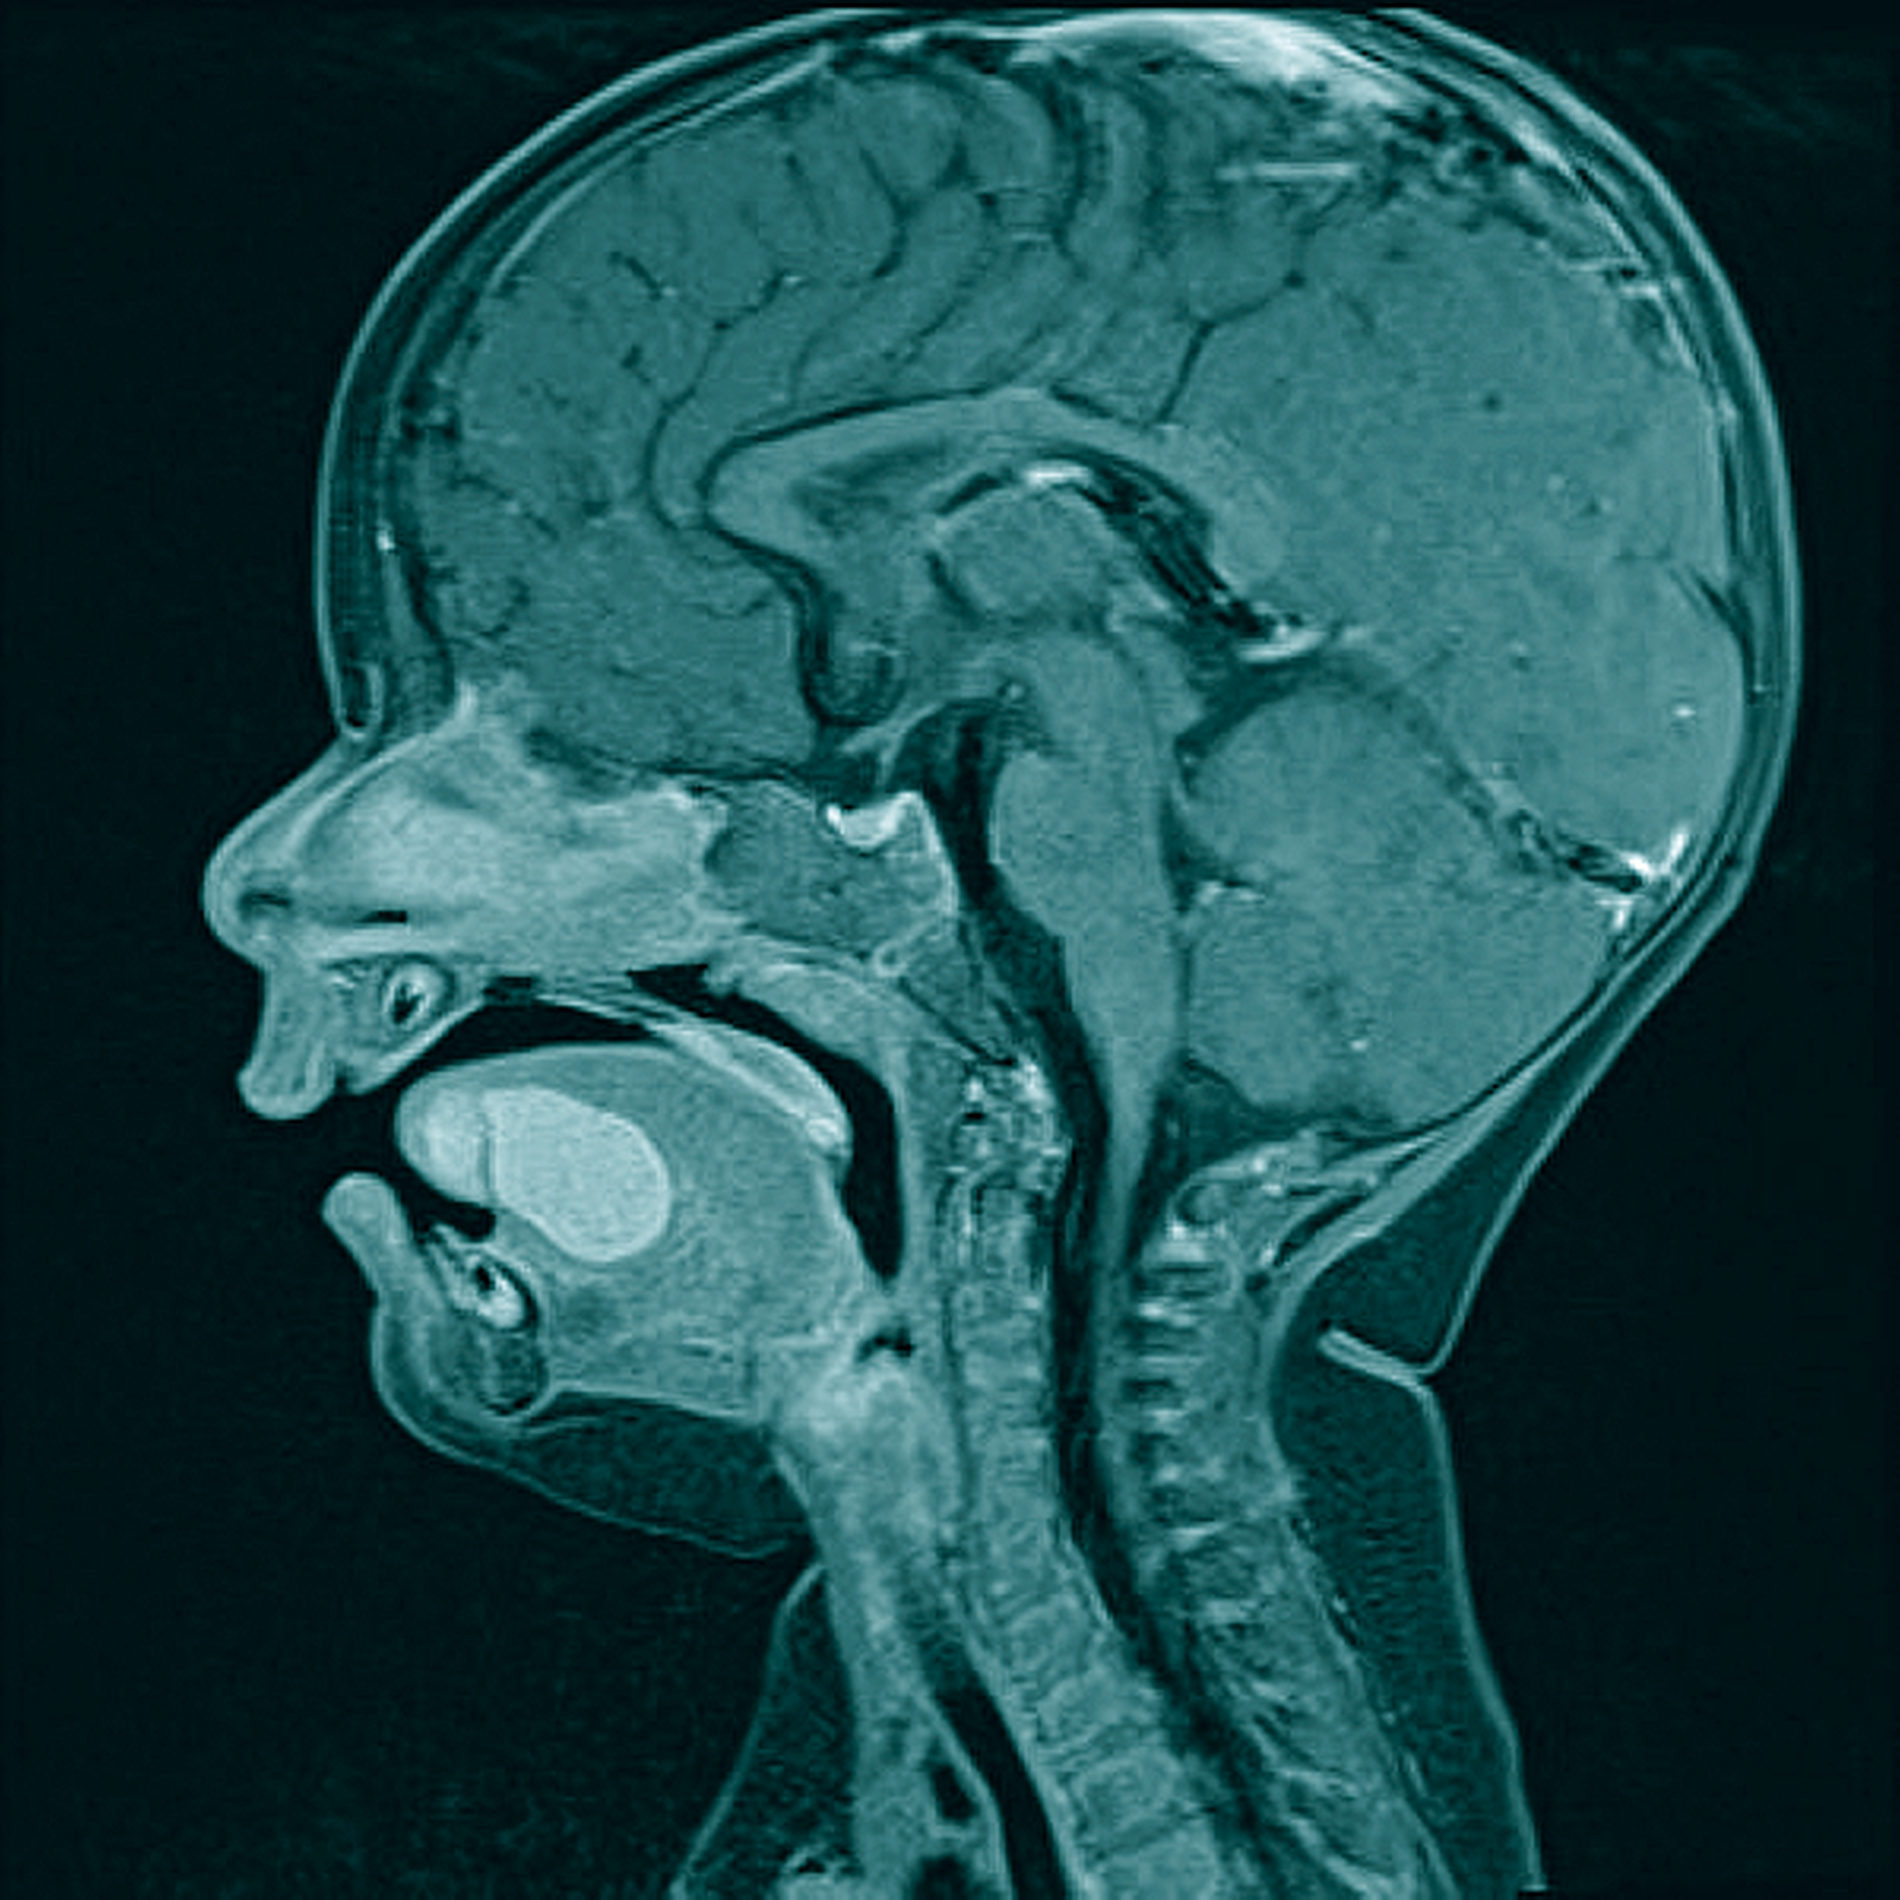

Zur erweiterten Diagnostik wurde in Sedierung eine Magnetresonanztomografie durchgeführt. Hier zeigten sich im Bereich des Zungenkörpers mit Übergang auf den Mundboden mehrere, konglomerierende zystische Läsionen (T1w nativ: flau hyperintense, Abbildung 2; T2w: hyperintense, teils diffusionsrestringiert, Abbildung 3) mit einer Gesamtausdehnung von 3,0 cm x 2,5 cm x 2,2 cm. Bildmorphologisch bestand der Verdacht auf eine Dermoid-Zyste, eine Foregut-Zyste oder ein zystisches Lymphangiom.